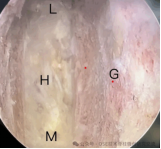

4.微创脊柱内镜技术:PELD+UBE+OSE

脊柱内镜技术是一项开展较早的脊柱外科微创技术,与传统开放手术相比,它是借助天然解剖间隙建立微创工作通道,解除神经压迫;对椎旁肌肉损伤较小,且能够最大程度地保留完整的脊柱结构,维持了术后脊柱的稳定,具有创伤小、出血少、恢复快、并发症少、疗效确切等优点。目前已开展椎间孔镜下髓核摘除术,单侧双通道脊柱内镜(UBE)下椎管减压术并处于区域内领先水平。皇冠娱乐城

在江苏省内率先开展了单孔分体式脊柱内镜技术(OSE),处国内领先水平。

单孔孔镜

单侧双通道技术

单孔分体式内镜下腰椎固定融合技术